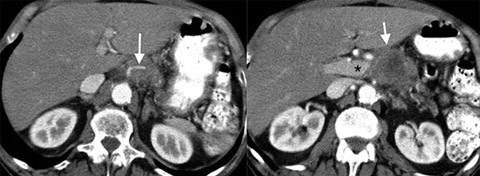

姓名:刘乐安(化名),76岁

国籍:美国

病症:胰腺癌III期(肿瘤/瘤/转移阶段),4.1X4.1X3,5cm

疗效:病人按照一般住院病人观察48个小时。手术后他没要求使用任何镇痛药物而且他的饮食在24小时之内就恢复正常饮食。病人在第二次消融后24小时出院并没有疼痛感和并发症。胰腺癌肿块已基本消失。